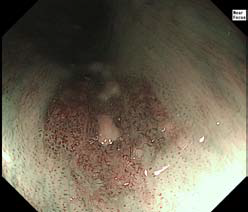

EVIS LUCERA ELITE中的窄带成像NBI与前几代相比,显着增加了可见距离。改善的对比度与这种增加的亮度相结合意味着NBI在帮助您进行病变检测和表征方面开辟了新的可能性。

EVIS LUCERA ELITE中的NBI提供了两倍于EVIS LUCERA SPECTRUM的可视距离。NBI的性能大大提高,开启了令人兴奋的新的临床应用,并加强了NBI作为GI胃镜检查标准的地位。